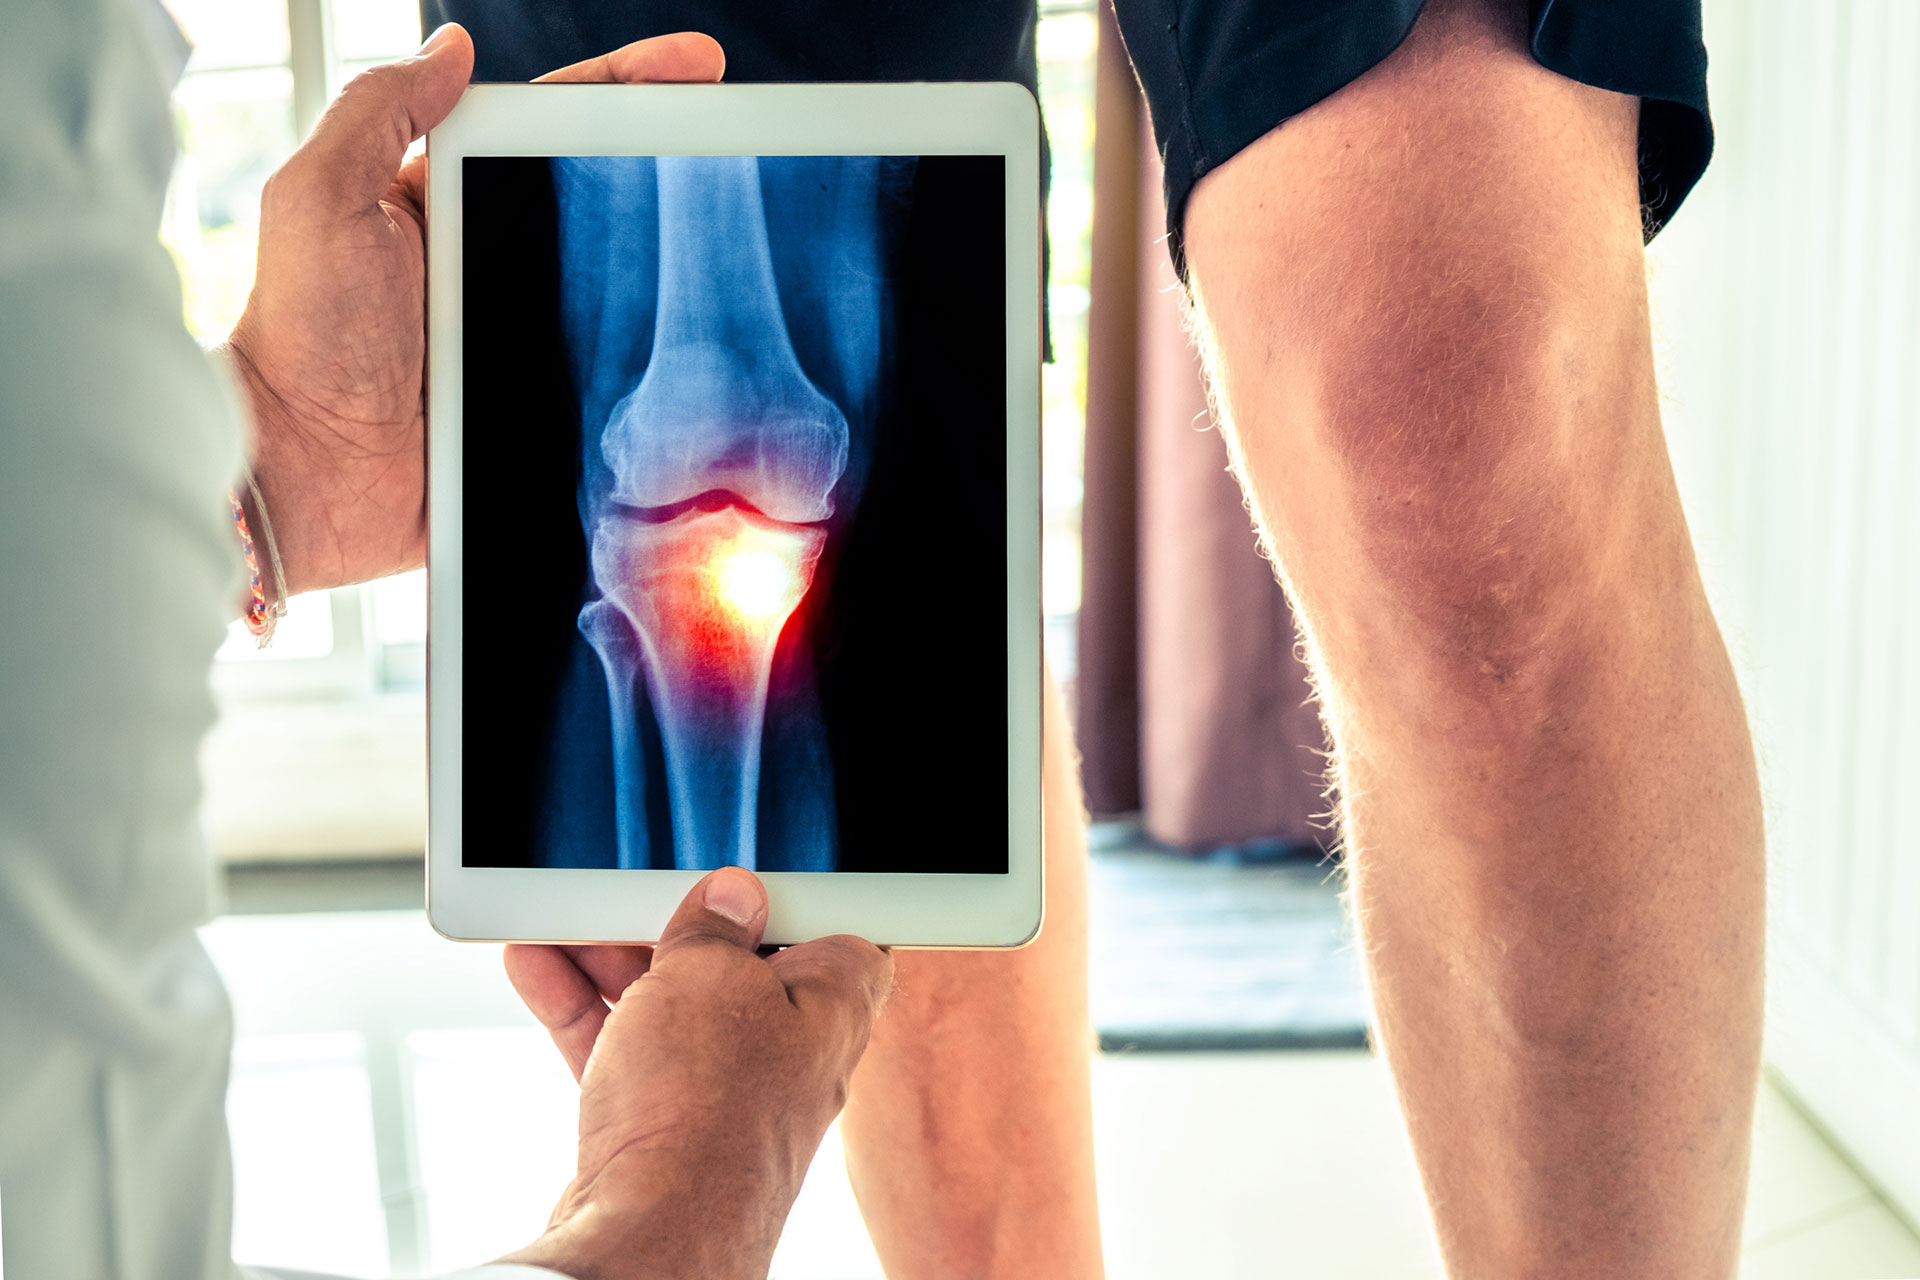

Spinal Procedures using Fluoroscopic (X-ray) Guidance

Spinal injections have become essential methods for diagnosing and/or treating spinal pain. The purpose of these injections is to deliver medication, usually a combination of a local anesthetic and a steroid anti-inflammatory medication, to a targeted tissue (like joint, nerve or disc), suspected or known to be a source of pain. The patient’s response to the placement of medication should indicate whether this targeted tissue is a significant source of pain and, if it is, should afford some degree of pain relief. These injections tend to be much more effective in controlling pain and keeping the pain under control than oral medications while avoiding systemic side effects such as gastritis and kidney problems. Pain relief is desirable in and of itself, of course, but it may be just as critical for patients to participate actively in a rehabilitative exercise program supervised initially by physical therapy. For many patients, training spine stabilization through exercise, will be key for safeguarding against having significant recurrent pain, which may ultimately be more of a problem than a transient episode of acute pain.

Before 1990, clinicians performed most injections “blindly,” that is, using anatomic landmarks that can be seen with the eye (observed) and felt with the hands (palpated). Such blind injections can be effective, but may miss the mark in some cases. Since 1990, our practice has been at the forefront of using image guidance to ensure the utmost precision with placement of medication with injections. Now this technologic method is standard practice.

The most commonly employed fluoroscopically guided injections are epidural steroid injections. With x-ray guidance, we can place a potent steroid anti-inflammatory medication in the epidural space that is connected with the spinal canal and the intervertebral discs. This procedure can control inflammation and pain related to the two most common painful conditions that we treat, namely lumbar disc herniations and lumbar spinal stenosis. We can treat cervical (in the neck region) and thoracic (in the mid-back) spinal conditions similarly, but “epidurals” are not commonly needed outside the lumbar spine. The weight of research and our experience bears out a good success rate with disc herniations close to 70%, particularly when there is leg pain (sciatica or radiculopathy) along with back pain. After more than 31 years of experience, we also know that the risks are minimal. Given this success rate and a documented negligible chance of a complication, epidural steroids offer an effective pain control option with minimal risk for disc herniations and most cases of spinal stenosis. The most common technique used is a transforaminal approach to the epidural space in which the injection is placed next to nerve as it exits the spinal canal through a “side door” (foramen). This approach tends to be the most efficient way to deliver the medication and may require placement at two levels or on both sides (bilateral). Alternately, we may opt to use a traditional caudal approach with access through the tailbone. The last approach that is rarely used by us nowadays is the interlaminar approach, which places the injection directly into the central canal between two vertebrae.

We can diagnose and treat lumbar facet joint pain due to spondylosis similarly, either with a steroid injection into the joint (intra-articularly) or by blocking small nerves to these joints (medial branch blocks) with local anesthetic diagnostically and, if warranted, with RFA therapeutically (as a treatment).

We can use these same approaches to treat facet pain in the neck less frequently and in the midback rarely.

Other procedures using fluoroscopic guidance are evolving. Genicular nerve blocks that involve the usual 2 sets of diagnostic anesthetic blocks followed by blocks with RFA can be very helpful in patients with knee osteoarthritis that is either inoperable or has already failed knee joint replacement surgery. RFA nerve blocks to other joints such as the shoulder and hip for osteoarthritis are in development.